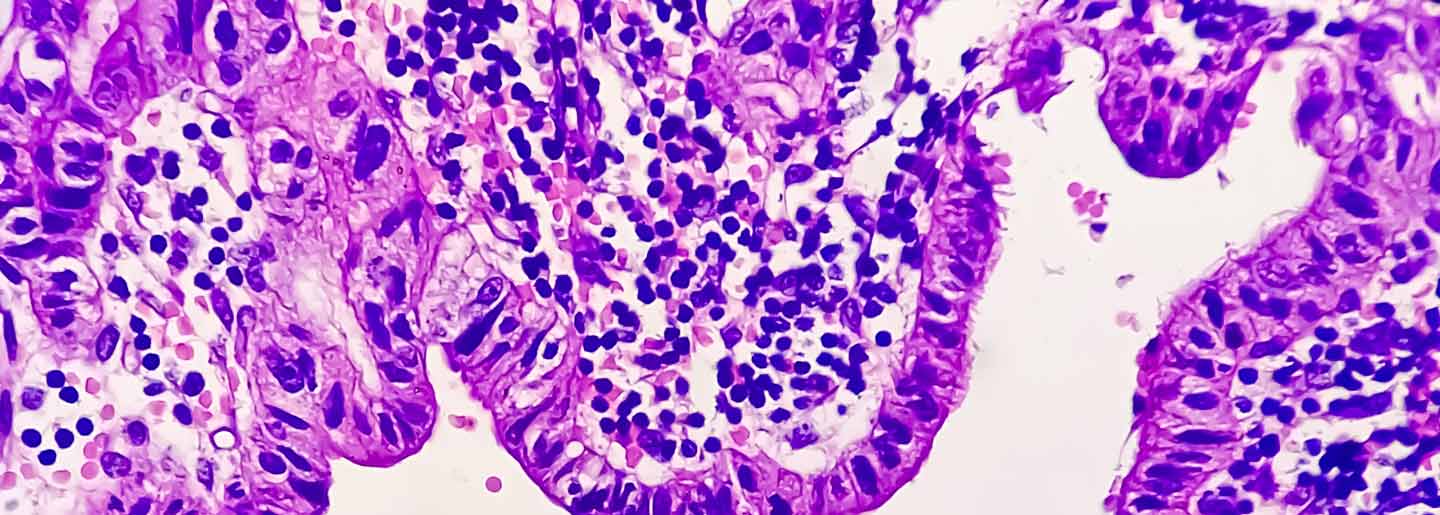

The researchers confirmed the importance of these molecular modifications in mouse experiments. They demonstrated that treatment of enzalutamide/abiraterone-resistant prostate tumors in mice with a Moffitt-designed ACK1 inhibitor called (R)-9b that targets ACK1 suppressed tumor growth, and reduced expression levels of ACK1, the androgen receptor and additional key genes regulated by the androgen receptor. Importantly, the researchers also showed that the expression level of ACK1 and the modified androgen receptor were higher in tissue samples from patients with prostate cancer than normal prostate tissue, and their expression increased throughout cancer progression.